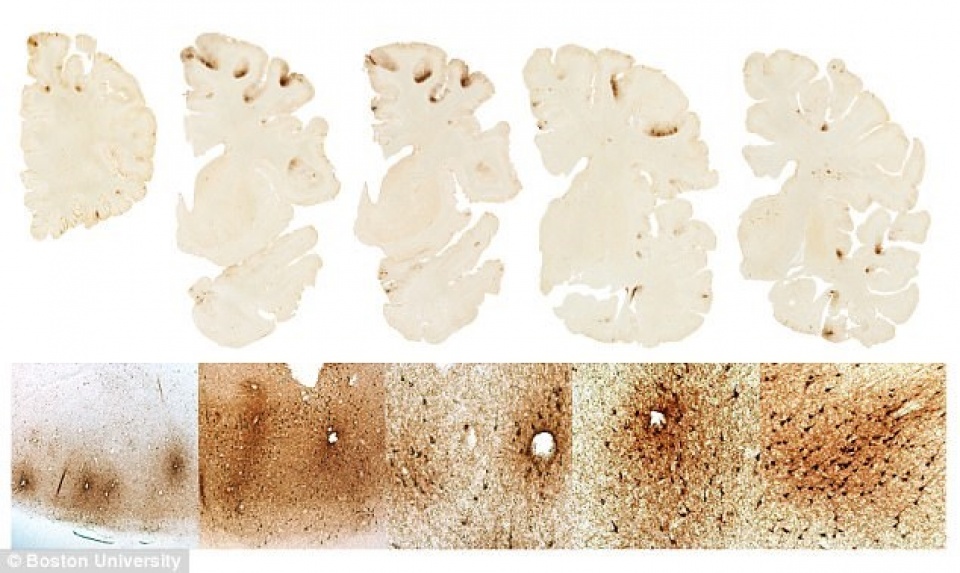

Nghiên cứu này đã phát hiện được sự gia tăng mật độ protein CCLL11 trong não bộ của những cầu thủ bóng đá bị mắc CTE đã chết, nhưng không tìm thấy nó ở trong não bộ của những người khỏe mạnh hoặc người bị bệnh Alzheimer.

Cho đến nay, CTE mới chỉ được chẩn đoán thông qua mô não của người chết nên kết quả nghiên cứu trên có thể giúp các nhà nghiên cứu tiến gần hơn đến việc phát triển một phương pháp chẩn đoán bệnh CTE đối với người sống bởi vì protein CCLL11 có thể được tìm thấy ở dịch não tủy.

| Các lớp cắt mô não. |

Việc phát hiện ra CCLL11 là một “dấu ấn sinh học” quan trọng nhưng cần phải tiếp tục nghiên cứu. Các nhà khoa học hy vọng rằng đây sẽ là một bước đi tiềm năng để phát triển các liệu trình điều trị và phương pháp phòng ngừa hội chứng CTE tốt hơn.

CCLL11 sau này có thể được sử dụng kết hợp với các “dấu ấn sinh học” và thủ thuật điều trị khác như chụp cắt lớp (PET) để chẩn đoán hội chứng CTE ở người sống.